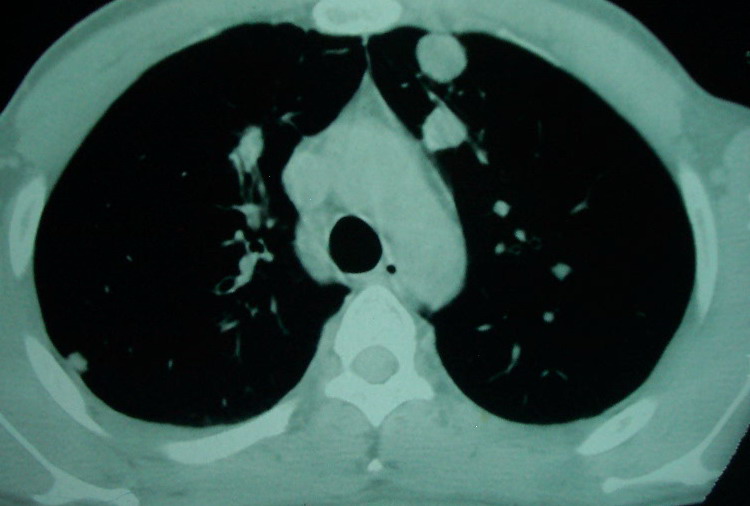

我看是不是可以两元化来解释,左肺下叶还是肺脓疡,而其余病灶考虑肺癌伴肺内转移,我看右肺上叶尖段病灶可见明显毛刺改变为原发病灶.

1、左下肺鳞癌伴两肺及纵隔淋巴结转移;

2、两上肺支扩伴慢性炎症。

鳞癌肺肺转移:厚壁空洞,洞壁厚薄不均,内似有壁结节,肺脓肿临床有无提示,血像如何?病灶周围很干净,没有明显渗出,很勉强?